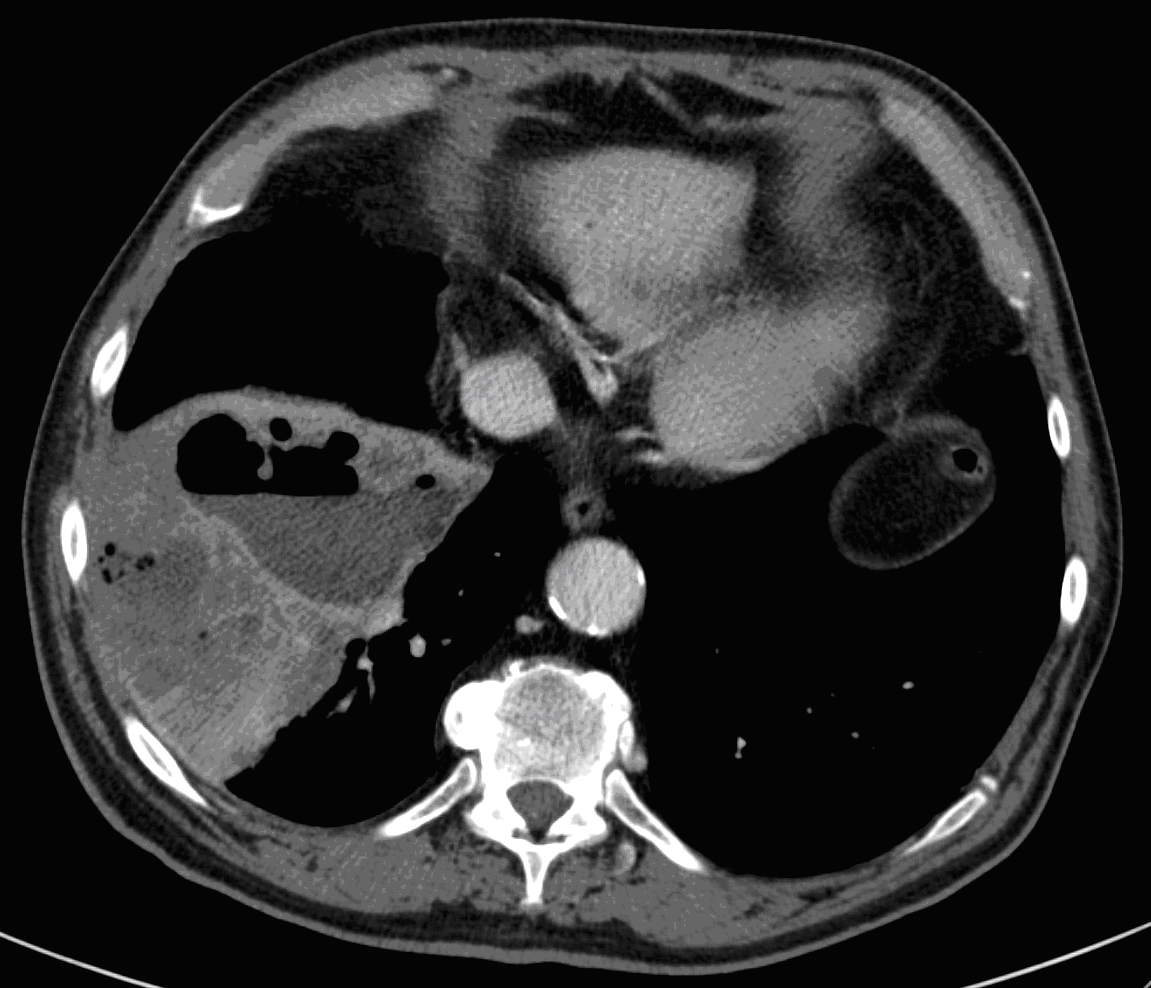

Image

6. c

6. d

64 year old man. Infiltration and abscess development in the right lower lobe.

c.) CT lung window, coronal reformat, d.) axial, mediastinal window. Extensive area in the right 8-9th segments without air, including many associated lesions of fluid density, with tiny air bubbles, larger air spaces and air-fluid level. The lesion has almost a triangular shape, its dorsal and ventral contours are arched, its peak points towards the lower pole of the hilum.